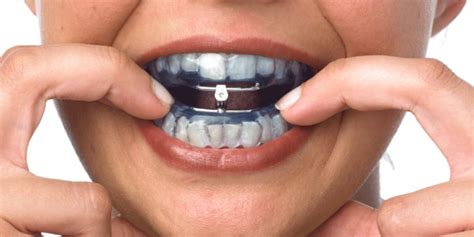

Diagnosi e terapia sindromi da apnee ostruttive notturne (Osas)

E' una patologia che sta diventando una vera e propria piaga sociale in quanto da statistiche potrebbe essere causa di circa il 20% degli incidenti automobilistici e che quindi coinvolge anche molti lavoratori nel settore dei trasporti.

I pazienti ,non potendo avere un sonno sufficiente e regolare per motivi anatomici e disfunzionali delle prime vie aeree, vanno incontro durante le ore diurne a narcolessie (addormentamento improvviso e scarsa lucidità nei riflessi) ed a frequenti cali di attenzione senza contare che le apnee che avvengono durante la notte (arresto del sistema respiratorio momentaneo ma ripetuto) possono essere concausa di malattie cardio vascolari e ictus.

Nella nostra rete ospedaliera esiste un protocollo diagnostico e terapeutico che coinvolge la figura del medico del sonno (OtorinoLaringoiatra), dello pneumologo ,del cardiologo , del neurologo e non per ultimo in ordine di importanza dell'odontostomatologo il quale , nelle forme lievi o moderate , puo' approntare dispositivi funzionali (apparecchi orali) che spostando in avanti la mandibola possono migliorare o risolvere questa problematica disfunzionale ed il russamento notturno.